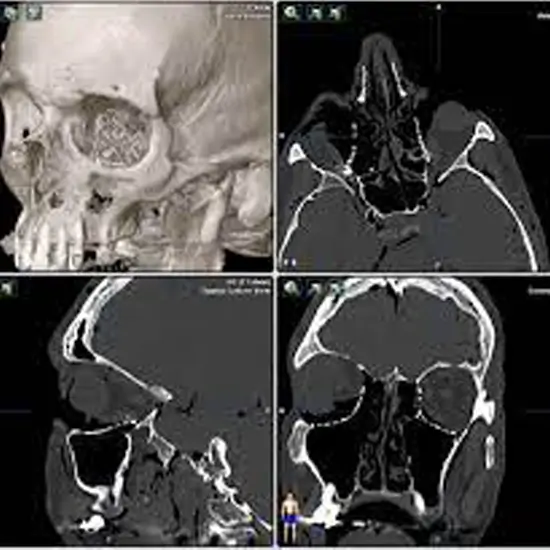

CT Orbit Axial/Coronal 3D is Computed Tomography Orbit Axial/Coronal 3-Dimension. It is an imaging procedure that obtains 3D images of the eye orbit. It is helpful for a doctor in detecting/diagnosing the problems in the orbits, eye sockets, eye, and the surrounding soft and bony tissue. It is also used to detect fractures in the orbit bones, the eye socket, and the presence of foreign objects in the eye socket or eye.

The scan is usually used to diagnose/ detect fractures in the bones of the orbit or eye socket, foreign objects in the eyes or orbit, any infections /inflammation in the area around the eyes, diseases of muscles, blood vessels, nerves, and tumors.